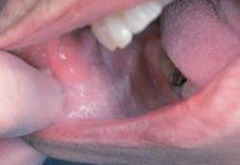

mucocele

-localized tissue swelling that increases and decreases in size most commonly on lower lip -severed salivary gland duct -mucous filled